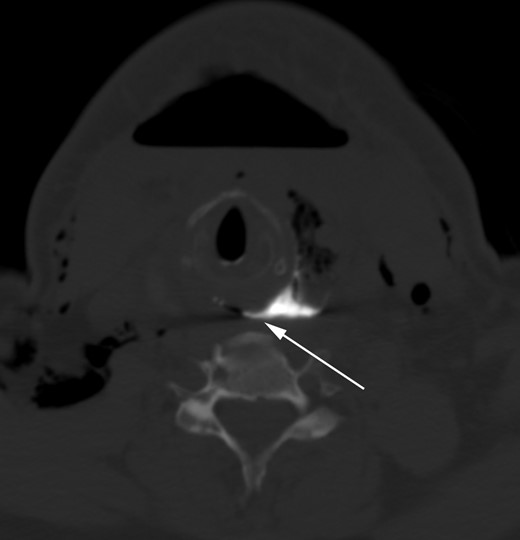

The patient soon demonstrated a recurrent esophageal leak (Fig. 2), which was managed by maintaining the patient nil per os, providing nutrition via a feeding tube, and applying negative pressure to the wound. The esophageal leak gradually resolved, as evidenced by multiple contrast esophagrams, permitting removal of the patient's drains. Prior to discharge from the hospital, barium esophagram showed no evidence of contrast extravasation.

Axial CT image of the neck after fluoroscopy barium swallow demonstrates contrast pooling in the lobectomy bed with a fistulous connection to the esophagus (white arrow; image shown using a ‘bone window’ to clearly outline the barium contrast).